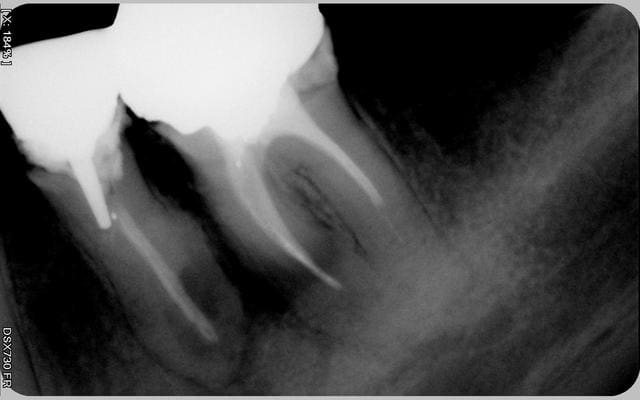

que faire ? je pense que la fistule vest vient de la prémolaire...

tenez ! cadeau

c'est le même praticien

vous noterez la position du pivot

et l'optimisme du praticien qui l'a posé dans une dent vivante

"coup de chance" ou "manque de pot" c'est à coté

je ne sais ce qui valait mieux